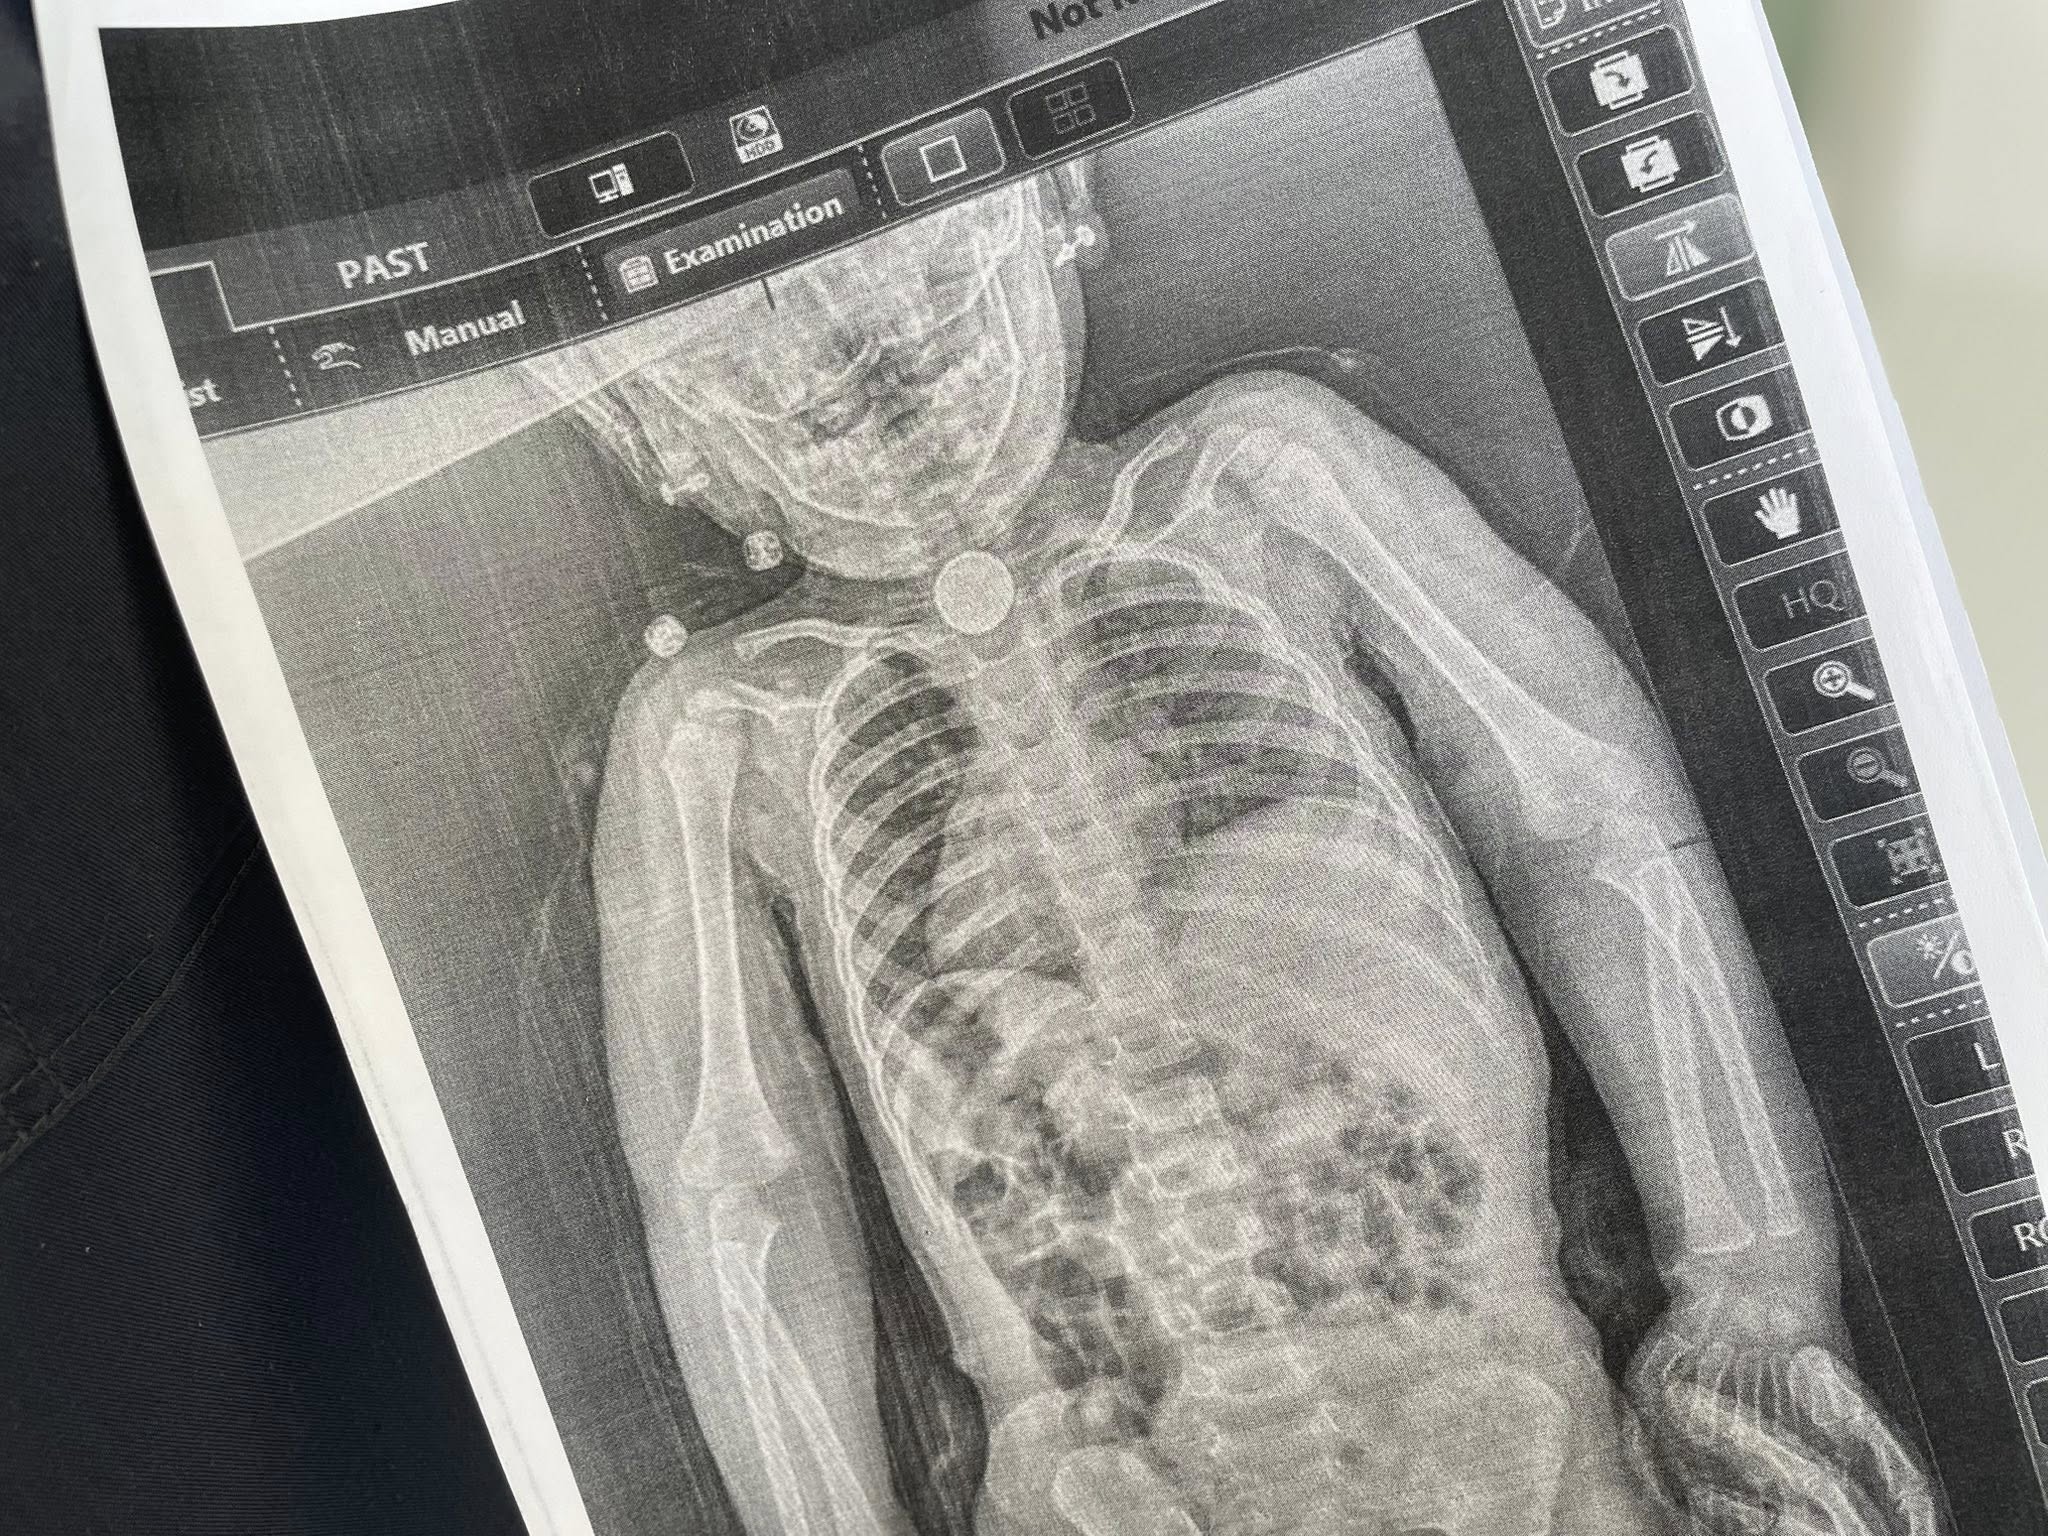

На початку весни в дівчинки з’явилися небезпечні для життя симптоми, зокрема блювання, відмова від їжі, покашлювання та свистяче дихання. Тоді батьки Софії відвезли її на нове обстеження, де їй зробили рентген. Завдяки цьому лікарі виявили стороннє тіло, яке застрягло в стравоході дитини.

«З’ясувалося, що три місяці в стравоході дівчинки була літієва батарейка діаметром 2,5 см. Навколо неї сформувалися набряк та гіпергрануляції слизової оболонки – ознаки тривалого ушкодження тканин.Хірурги діяли максимально обережно: батарейка була щільно зафіксована, а будь-яка маніпуляція могла призвести до перфорації стравоходу, тобто його розриву. За допомогою ларингоскопа та спеціальних інструментів лікарям вдалося безпечно видалити сторонній предмет», – пояснили медики.